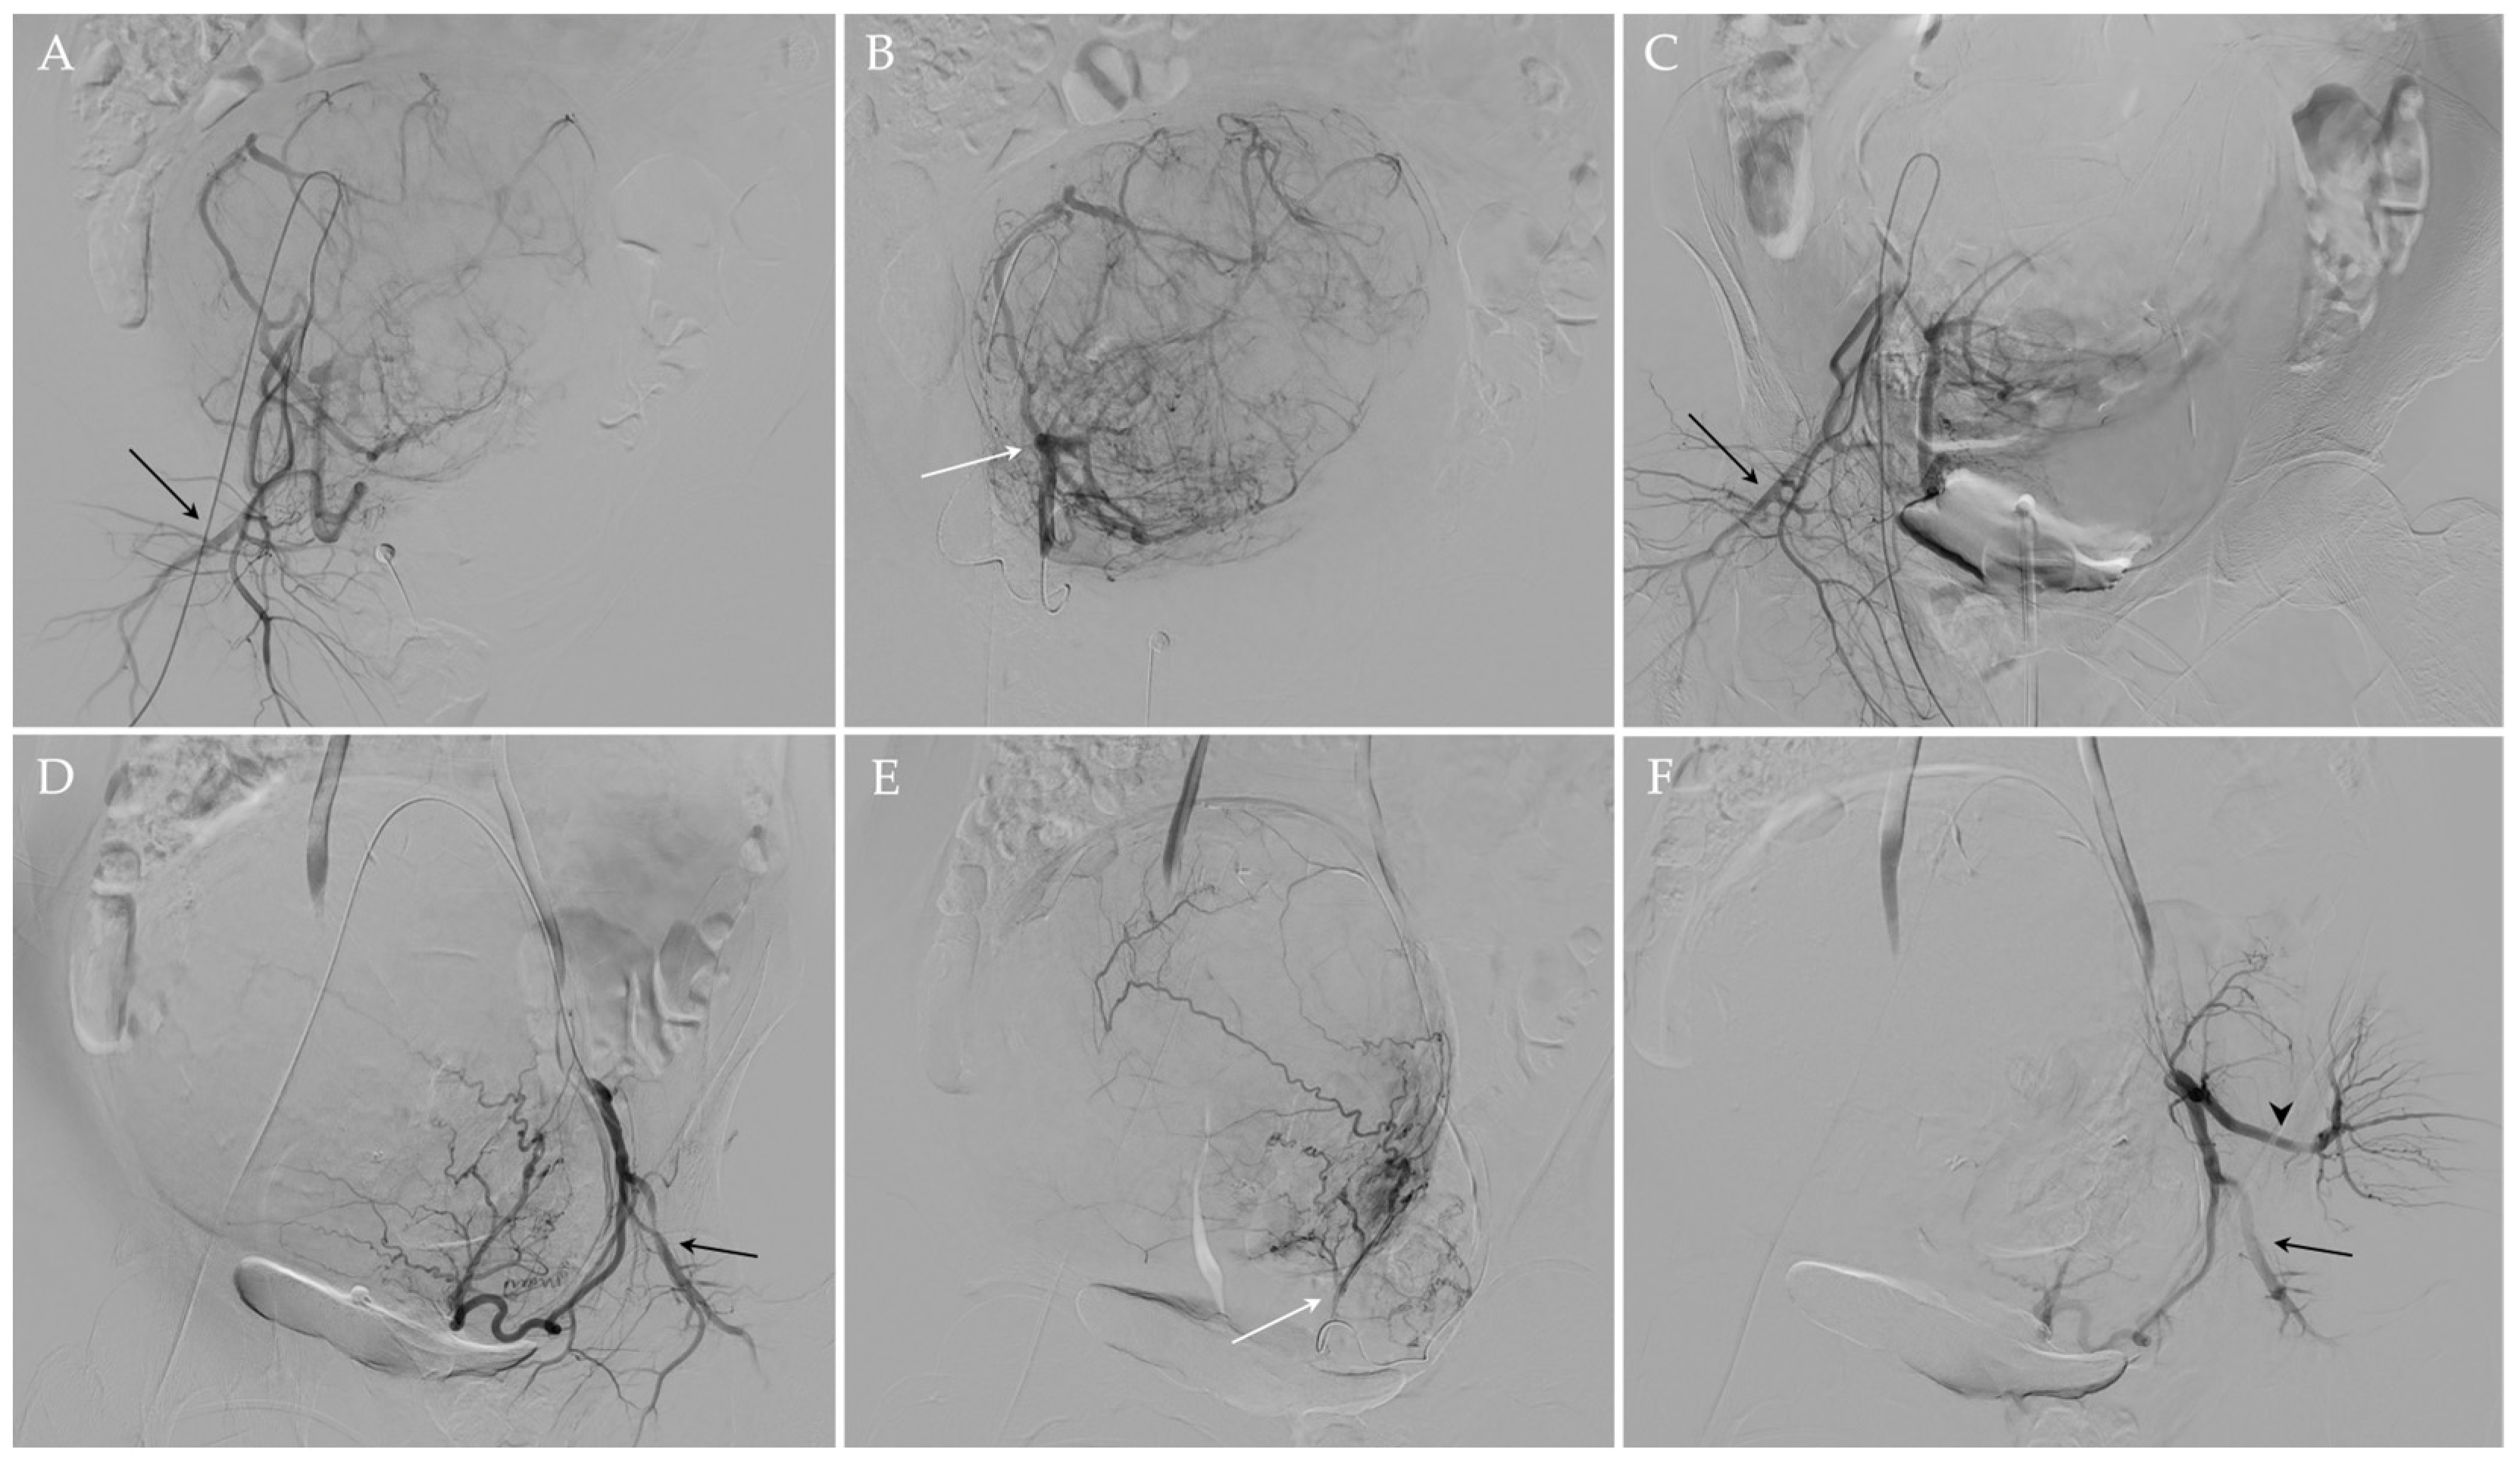

UAE procedure was performed under fluoroscopic guidance and according to the standards of practice [57,58]. In particular, after the administration of local analgesia (Lidocaine 1%), a 5 French (Fr) arterial sheath was placed in the left common femoral artery under ultrasonographic guidance. Then, internal iliac arteries were selectively catheterized using Cobra diagnostic catheter (4 or 5 Fr) (Terumo®, Tokyo, Japan) and a 0.035” angled guidewire (Terumo®, Tokyo, Japan); a subsequent diagnostic angiogram was carried out to evaluate the anatomy of uterine arteries and to confirm that no vascular anomalies are present and other organs are not affected. Subsequently, the uterine artery is selectively catheterized with a microcatheter (2.7 F) and a microwire (0.021”) (Progreat; Terumo®, Tokyo, Japan), and distal embolization was achieved using microspheres 500–700 μm or 700–900 μm in diameter (Embosphere®; Merit Medical/Biosphere, Roissy, France) or 500–710 μm nonspherical particles (Contour®; Boston Scientific, Natick, MA, USA). Once the embolization is completed on one side, the process is repeated on the opposite side in the same fashion. In the presence of a utero-ovarian anastomosis, a micro-coil was positioned in advance to protect the ovary. At the end of the procedure, a final angiogram was obtained to confirm the correct occlusion of both uterine arteries (Figure 3). The specific embolic agent and the number of particles used were at the discretion of the interventional radiologist, depending on the fibroid size, and the endpoint of the embolization procedure was complete or near complete stasis of blood flow in the uterine artery. The mean number of vials used per procedure was 3.8 (range 1–9), in agreement with the reference works [59].

Figure 3.

UAE of the same patient. Using a transfemoral approach, the preliminary angiographic study (A,D) allowed an adequate visualization of the right and left uterine arteries, which appeared hypertrophic, and the right and left pudendal arteries (black arrows in (A,D), respectively). After the superselective catheterization of the right and left uterine arteries (white arrows (B,E) respectively), embolization was performed. At the end of the procedure, the occlusion of both uterine arteries was documented and the patency of both pudendal arteries (black arrows in (C,F)) and of the left gluteal artery (black arrowhead in (F)) was appreciated.